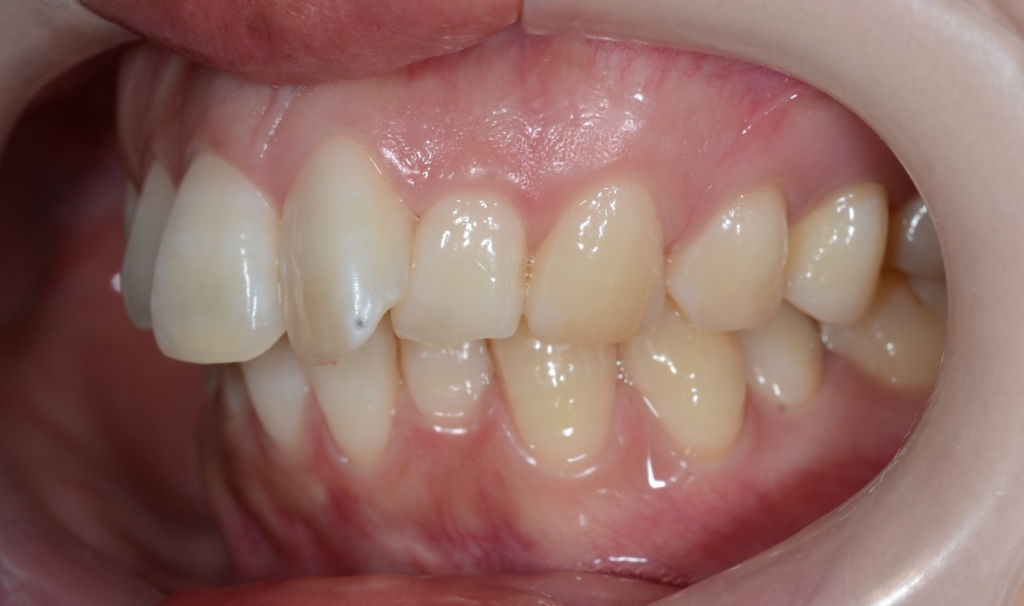

【Before】

レントゲン写真を確認すると、

この患者さんの場合、

【診断】

#1.上顎前突

#2.顎と歯の大きさの不調和による叢生

#3.ガミースマイル

と診断しました。

*歯並びの写真で見ると「出っ歯」であるとは分かり難いですが、頭部全体のレントゲン写真を見ると、出っ歯であることがハッキリと分かります。